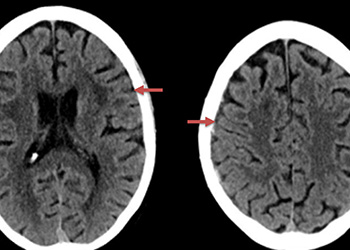

An MRI confirmed diffusion and FLAIR positive ischemic strokes within the deep periventricular white matter compatible with a “watershed” distribution of injury (Figure 3).

Figure 3. A) MRI Diffusion and B) FLAIR sequence confirm ischemic damage in the right periventricular deep white matter “Watershed” territories.